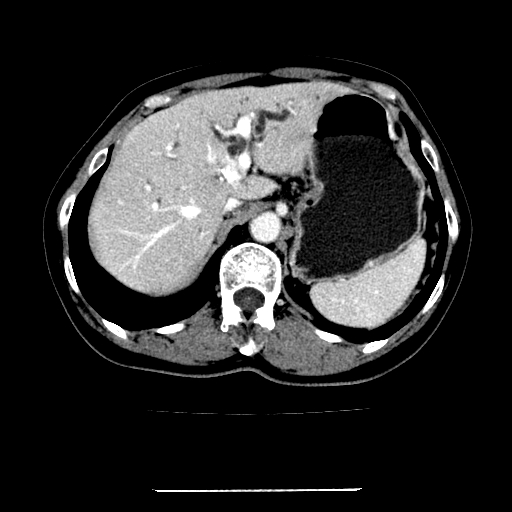

女,67岁,上腹部疼痛一周伴皮肤黄染,无发热。

左叶肝内胆管结石,并远端肝内胆管扩张。

考虑:肝内胆管结石继发肝内胆管扩张,右肾旋转不良。

支持肝内胆管结石并肝内胆管扩张。

肝内外胆管结石并肝内胆管扩张。

1、肝门高密度影下层面和胰头层面可见轻度胆管扩张,而静脉和延迟期均未见扫描完胰头,不能完全排除胰头占位。2、肝门部高密度影,考虑钙化或结石。

考虑肝门胆管癌伴门脉左支受侵包埋,建议mrcp进一步检查。